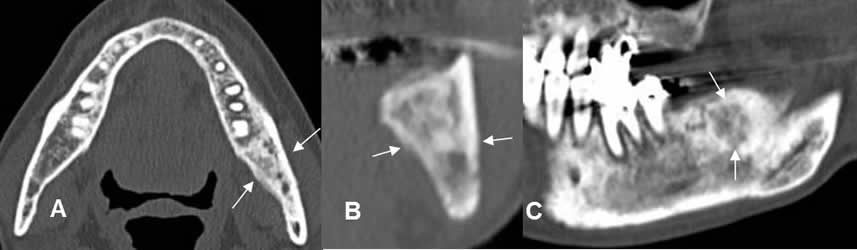

Fig 72. Tumor.

A: TAC axial en ventanea ósea y B: TAC axial en ventana de tejido, con contraste. Lesión lítica que compromete la sínfisis mandibular, que se asocia a masa de tejidos blandos, que capta el contraste. Corresponde a tumor escamocelular.